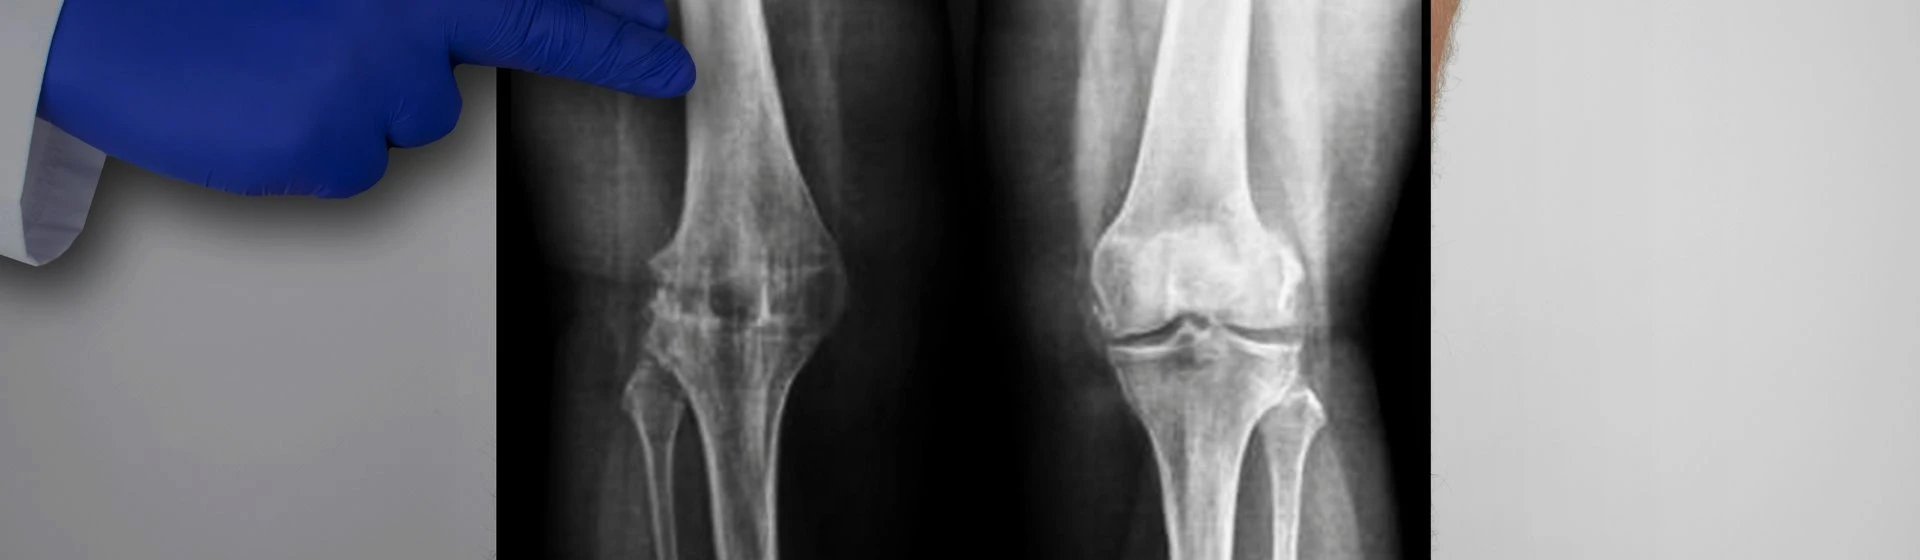

Рентген колен в частной клинике Оксфорд Медикал Киев

Цифровая рентгенография ног – радиографическая методика, используемая для обнаружения патологическиих очагов в конечностях, оценки их размеров, очертаний и степени поражения прилегающих структур. Это самый распространенный, быстрый и информативный метод диагностики их повреждений. Постоянные высокие нагрузки на конечности приводят к частым их травмам и разного рода болезням, выявить которые помогает рентген.

• травмы (переломы костей, вывихи суставов, разрывы сухожилий);

• артрит;

• артроз;

Для обследования пациентов применяется современный цифровой рентген Multix Select DR, производства корпорации Siemens. С его помощью врачи получают необходимую для диагностики информацию, при этом пациент подвергается минимальному облучению – в разы меньшему, чем на старых рентгеновских аппаратах.

Информация, полученная в результате цифровой рентгенографии, сразу же доступна для анализа врачом, может записываться на цифровые носители и пересылаться по электронной почте. Также печатается снимок ноги, который выдается на руки пациенту.